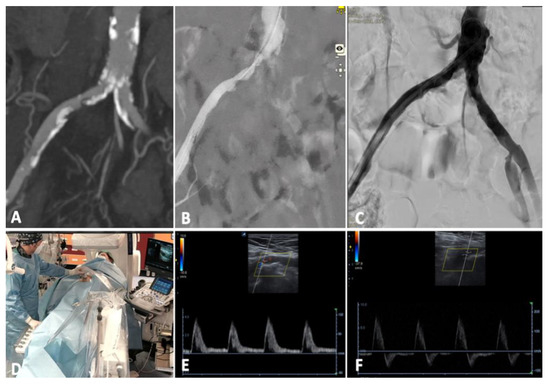

Case 1. The patient was a 74 year-old male with a preocclusive calcified lesion of the proximal right external iliac artery and an occluded superficial femoral artery. He referred 20 m walking distance and nocturnal rest pain of the right leg (Rutherford category 3/4) [8] with an ABI of 0.45; he was previously treated by an endovascular abdominal aortic aneurysm repair (EVAR) therefore, contralateral femoral access was not feasible. A percutaneous left brachial access with 6 Fr introducer sheath was performed to avoid the puncture of an extremely calcified right common femoral artery (~50% stenosis). In this case, the right groin was examinable by DUS during the entire procedure in the absence of any introducer sheath. The preoperative DUS showed a monophasic waveform at the level of the common femoral artery Figure 3E).

Due to the extensive vessel calcifications, the completion angiogram showed unclear imaging (good flow in terms of contrast medium velocity with a suboptimal arterial vessel filling) despite the use of two different C-arm projections. EVUS showed an optimal result with monophasic flow changing to multiphasic (Figure 3F). Neither DCB, nor stenting was necessary. The postoperative ABI was 0.8 with a walking distance > 1 km; therefore, any procedure of the superficial femoral artery was not required. The patient was discharged with double anti-platelet therapy (DAPT) for three months, followed by lifelong single anti-platelet therapy with 100 mg of cardioaspirin and statins. Primary patency was maintained at follow-up DUS controls, with the same waveform for up to 18 months.

In this case, EVUS clarified doubts about different angiograms and represented the final assessment to avoid stenting of a calcific plaque close to the hypogastric artery, potentially at risk for complications.

Figure 3. Case 1, right iliac external subocclusion, treated by intravascular lithotripsy without stenting from brachial access. (A) Preoperatory CT scan; (B) initial angiogram; (C) completion angiogram; (D) EVUS with preoperative (E) and postoperative (F) waveforms, changing from monophasic to biphasic flow.